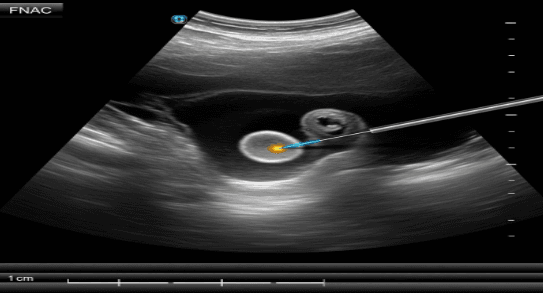

The term “USG Guided” signifies that the entire process is done under the guidance of an ultrasound (sonography). The ultrasound tool provides a continuous picture of your body’s interior, making it possible for the physician to accurately direct the needle to the intended spot. Thus, the USG FNAC Test is very accurate and secure.

- Sample Collection: After the anesthesia has taken effect, the physician will puncture the epidermis with an extremely slender needle and, by looking at the ultrasound monitor, will steer it straight to the intended tumor. The needle is then very gently moved to take a slice of cells, which are then sucked into the syringe that is connected to it. To make certain that there are sufficient cells, this can be done several times.